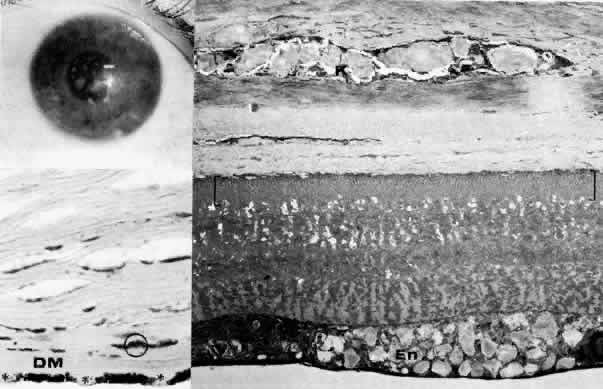

Congenital Hereditary Endothelial Dystrophy

Initially described by Maumenee173 in 1960, this congenital disorder of the endothelium is characterized clinically by diffuse, bilaterally symmetric corneal edema (Figs. 5 AND 15; Color Plate 1J). The autosomal recessive variety is present at birth and is relatively stationary. Symptoms of discomfort are not prominent despite profound epithelial and stromal edema. Nystagmus is common.174 A dominantly inherited form is less severe, developing in the first or second year of life, and, in contrast to the recessive variety, progressive photo(text continues on p. 27) phobia and tearing are the initial symptoms. Nystagmus is generally absent.174 As in all instances of congenital corneal clouding, it is important to rule out congenital glaucoma.

Fig. 15. Congenital hereditary endothelial dystrophy. Top left. Clinical photograph of eye of a 14-year-old male with severe form of the dystrophy shows diffuse ground-glass stromal opacification. Top middle. In a mildly affected 20-year-old female, the cornea has moderate diffuse haze and visual acuity is 20/200. Top right. On slit lamp biomicroscopy, diffuse edematous thickening of the corneal stroma is evident in same patient as top middle photograph. Middle right. Light microscopy of a case with uniformly thickened (approximately 35μm) Descemet's membrane (DM) covered posteriorly by extremely attenuated endothelial cells (arrowheads). S, posterior stroma; AC, anterior chamber (hematoxylin-eosin, × 600). Bottom left. Transmission electron micrograph of same case as middle right micrograph reveals anterior portion of Descemet's membrane (DM) to have normal thickness and banded structure. The markedly thickened (approximately 20 μm) posterior layer exhibits both 55 nm and 110 nm banding (circled) interspersed with homogeneous material. En, endothelial cell; AC, anterior chamber; S, posterior stroma (× 9200). Bottom right. At higher magnification, the abnormal posterior zone is seen to consist of multiple laminations of basement membrane-like material (*) and fine filaments. En, endothelial (× 42,000).

The degree of edematous corneal clouding varies from a mild haze to a milky, ground-glass opacification. Epithelial microbullae may be obvious, and stromal thickness may be increased threefold or more. Uniform thickening of Descemet's membrane is sometimes evident on clinical examination, but no guttata are apparent. Interstitial inflammation and secondary vascularization are absent. There are no definitely associated ocular or systemic abnormalities.

Histologic study175–181 reveals nonspecific anterior and stromal changes consistent with long-standing secondary edema: basal epithelial cell swelling, basement membrane thickening and disruptions, and irregularities of Bowman's layer with pannus formation. However, it may be significant that, in some cases, ultrastructural examination discloses greatly enlarged stromal collagen fibrils sometimes measuring as much as 60 nm in diameter. Descemet's membrane is uniform in a given specimen; it may display diffuse thinning of 3μm to massive thickening of 40 μm (normal thickness is 3 to 5 μm in neonates and 8 to 10 μm in adults). The anterior banded layer of Descemets membrane is always present and of relatively usual thickness; however, the posterior layer consists of multilaminar basement membrane-like material with fine filaments and of collagen fibrils with a 55- and 110-nm banded configuration. With the exception of the lack of guttata, these findings are similar to those in Fuchs' dystrophy and thus represent another example of posterior collagen layer formation by either primarily or secondarily abnormal endothelium.18,41,43,181, It is postulated that in cases with thin Descemet's membrane, complete endothelial loss occurred in utero such that only the fetal anterior portion of Descemet's membrane was secreted.180 In contrast, cases exhibiting thickened Descemet's membranes may be the product of dystrophic but persistent endothelium having secreted a hypertrophic posterior collagen layer.

The frequent finding of enlarged stromal collagen fibrils suggests some primary developmental abnormality of both keratocytes and endothelium, thus perhaps qualifying this disorder as another example of mesenchymal dysgenesis.22